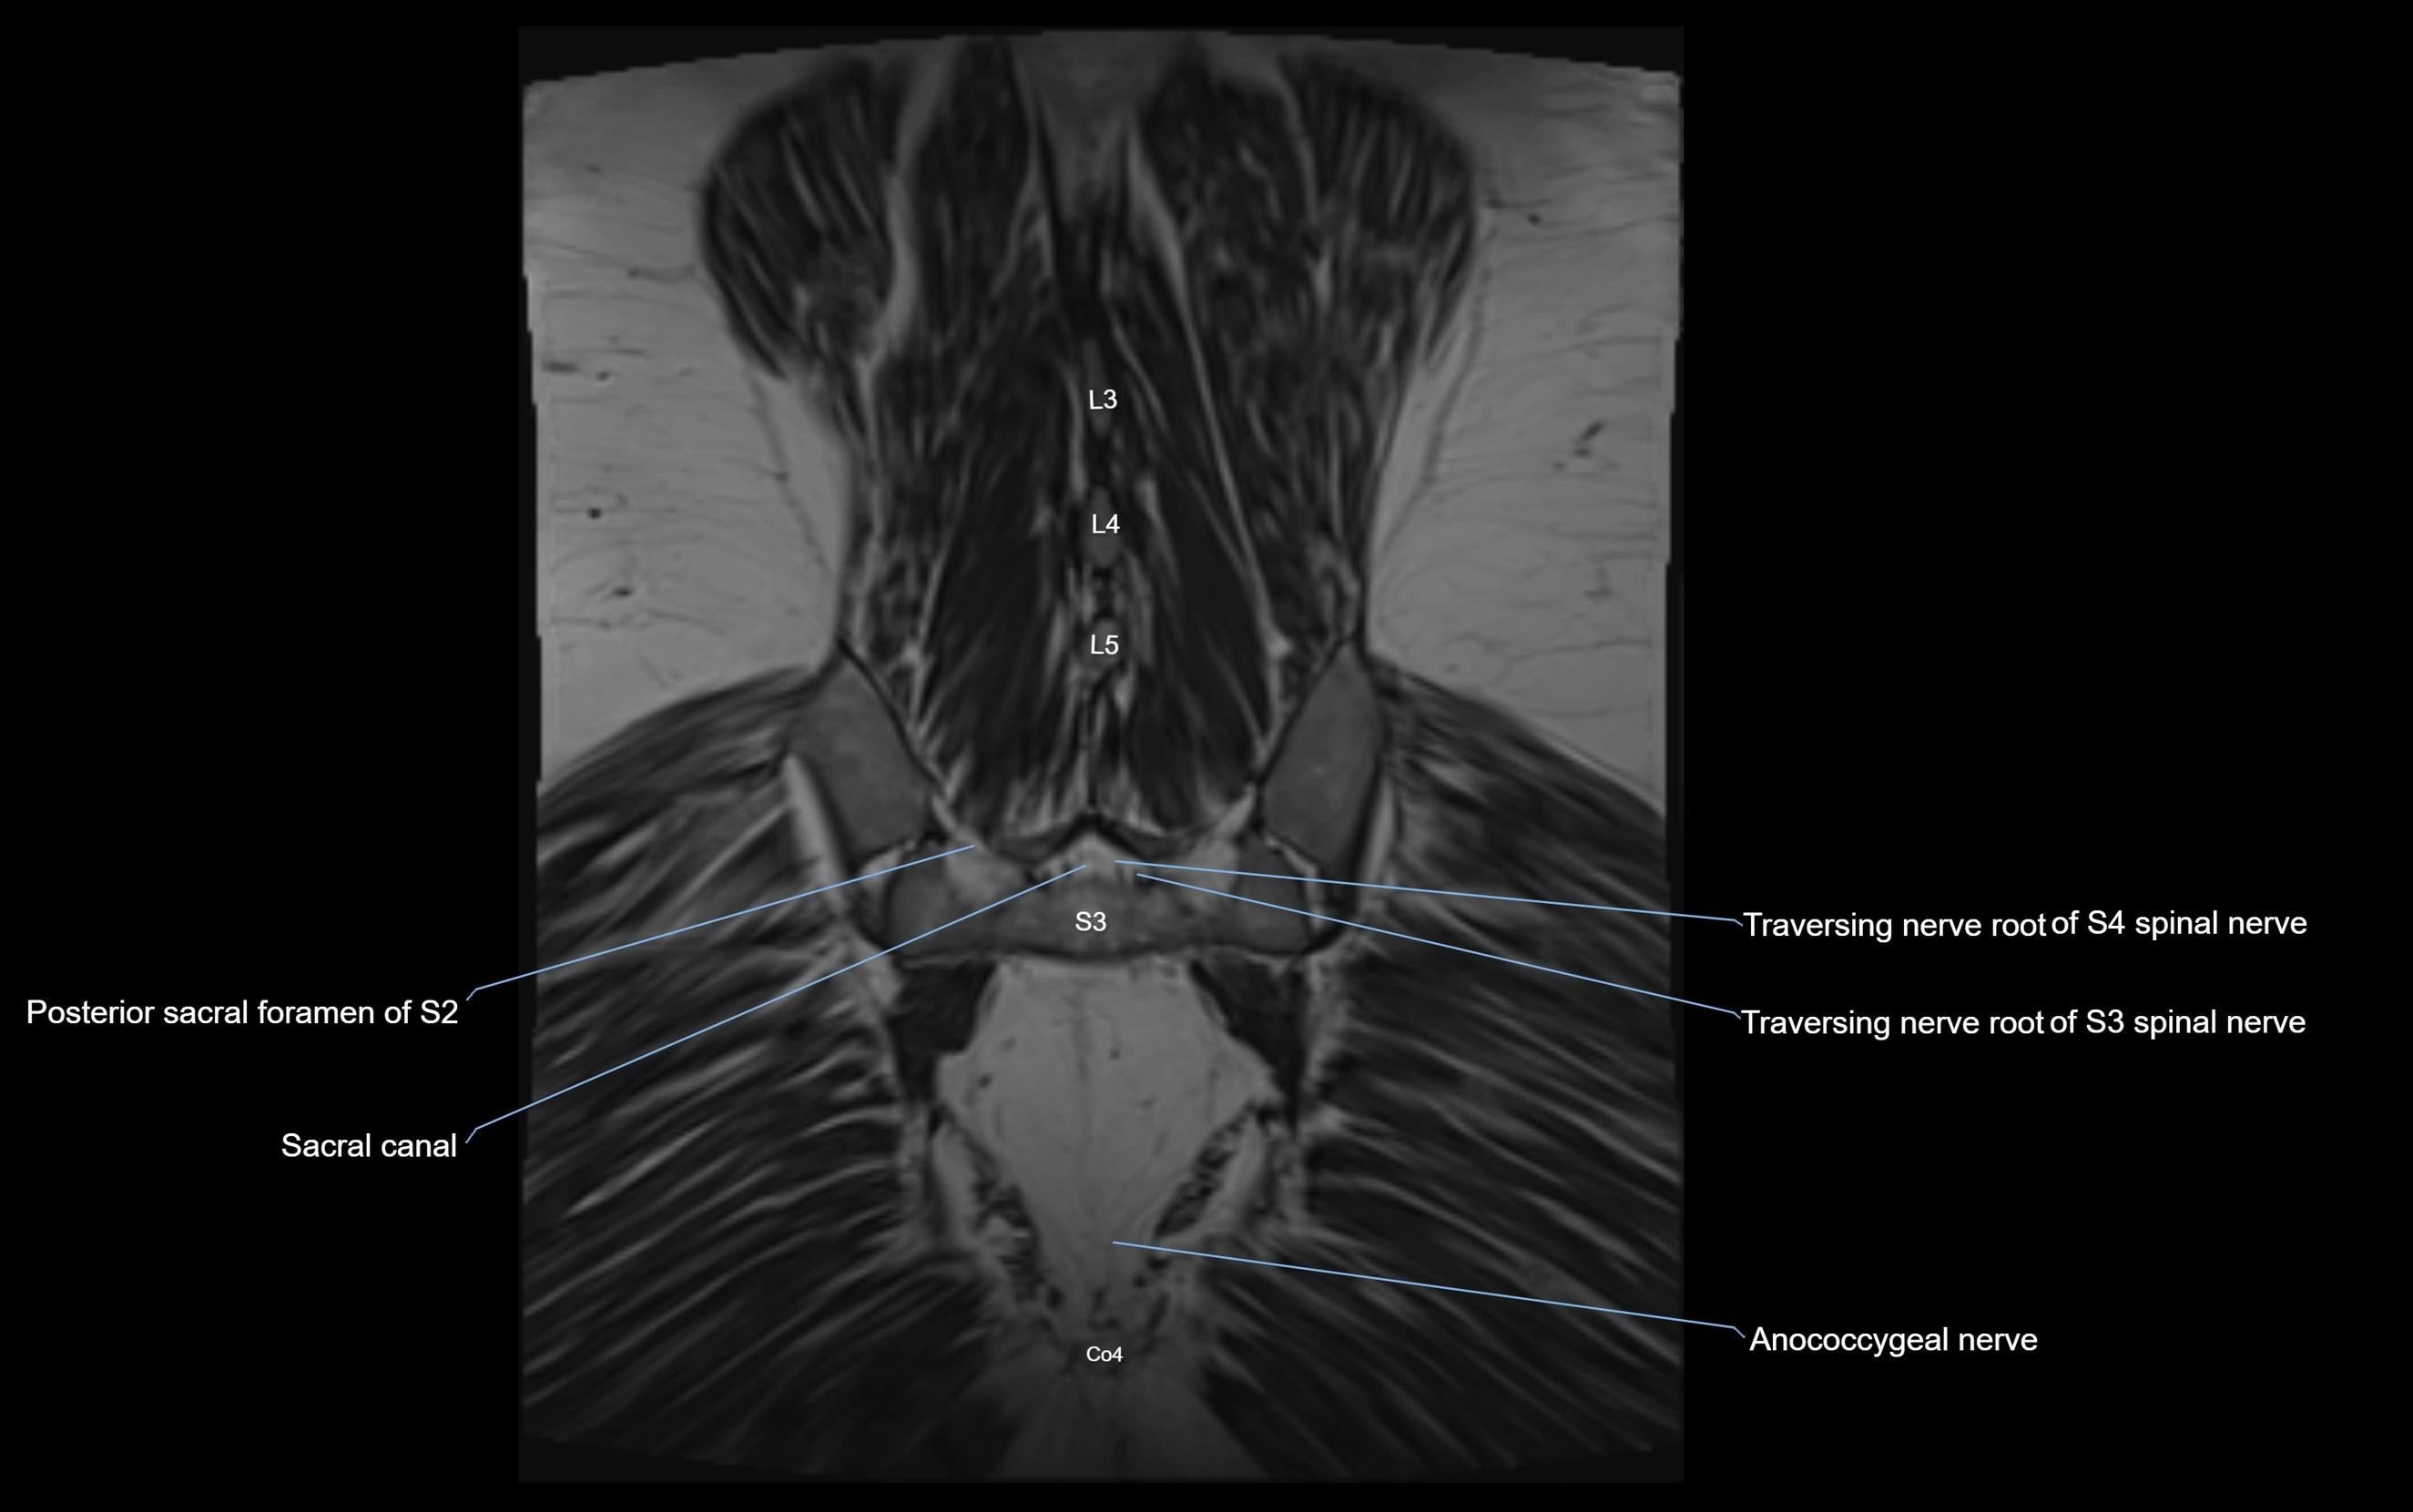

MRI image

image